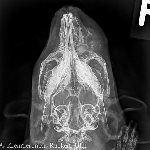

Etwas schwieriger mag die Beurteilung der Kopfröntgenaufnahme des Meerschweinchens sein. Wenn man aber die rechte mit der linken Kopfhälfte vergleicht, wird man schnell erkennen, dass sich der Oberkieferknochen rechts fast völlig aufgelöst hat. Die damit verbundenen Qualen müssen geradezu unvorstellbar gewesen sein. Diesem Patienten konnte nur noch durch die sofortige Euthanasie geholfen werden.

Sie werden mir zustimmen, dass diese beiden Röntgenbilder alles andere als unnötig waren, denn sie brachten uns den diagnostisch und prognostisch entscheidenden Erkenntnisgewinn. Das wissen wir jetzt, denn im Rückblick hat man ja bekanntermaßen immer eine hundertprozentige Sehschärfe. Wussten wir das schon vorher? Natürlich nicht, denn sonst wären wir ja Hellseher und hätten folgerichtig auch gleich aufs Röntgen verzichten können.